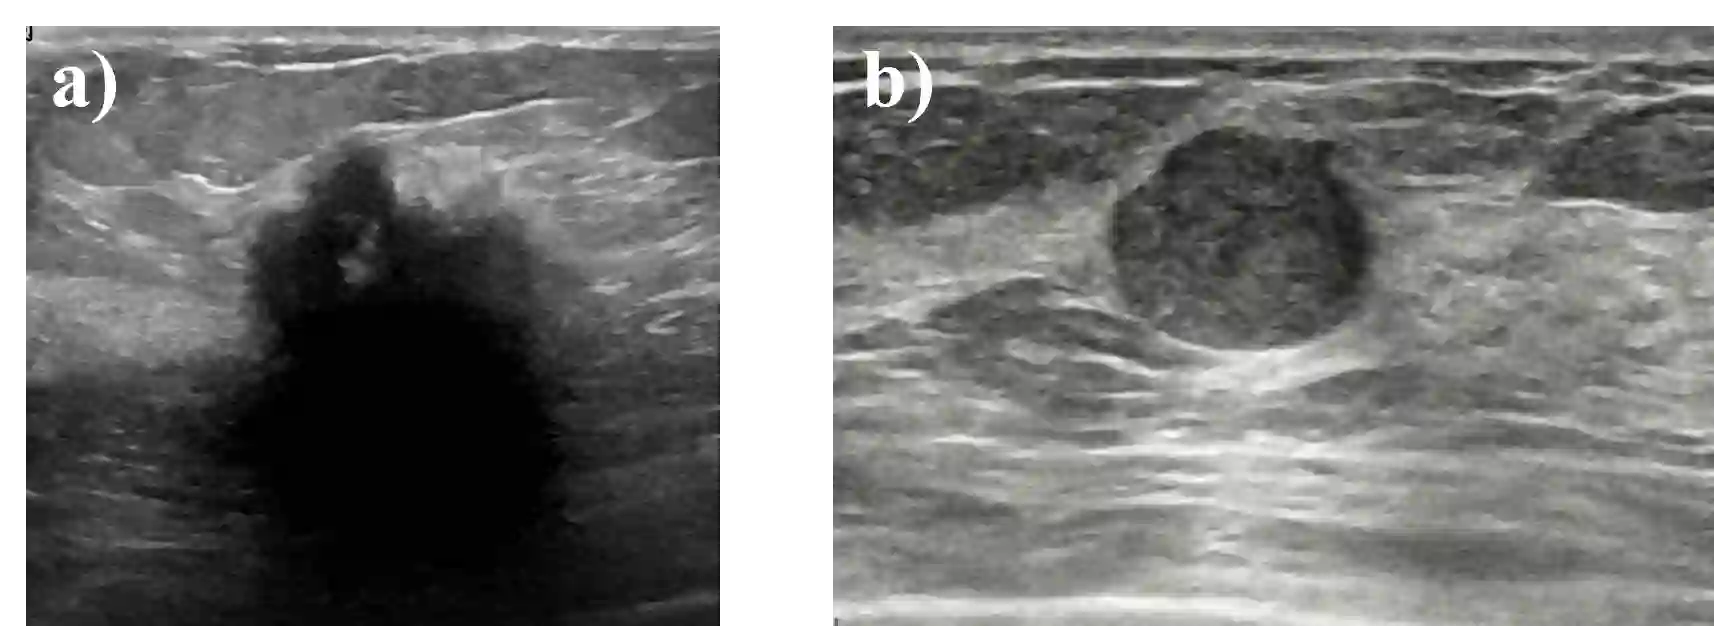

Standard classification methods based on handcrafted morphological and texture features have achieved good performance in breast mass differentiation in ultrasound (US). In comparison to deep neural networks, commonly perceived as "black-box" models, classical techniques are based on features that have well-understood medical and physical interpretation. However, classifiers based on morphological features commonly underperform in the presence of the shadowing artifact and ill-defined mass borders, while texture based classifiers may fail when the US image is too noisy. Therefore, in practice it would be beneficial to select the classification method based on the appearance of the particular US image. In this work, we develop a deep meta-network that can automatically process input breast mass US images and recommend whether to apply the shape or texture based classifier for the breast mass differentiation. Our preliminary results demonstrate that meta-learning techniques can be used to improve the performance of the standard classifiers based on handcrafted features. With the proposed meta-learning based approach, we achieved the area under the receiver operating characteristic curve of 0.95 and accuracy of 0.91.